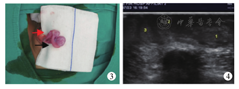

例2 男,1岁2个月,因右侧阴囊空虚、左侧阴囊内肿物入院,诊断为"右侧异位睾丸"。体格检查时患儿右侧阴囊空虚,于右侧阴囊及腹股沟区均未触及睾丸,左侧阴囊发育可,阴囊内下方可触及睾丸,大小约10 mm×8 mm×7 mm,睾丸上方可触及两个类睾丸样肿物,最上方大小约8 mm×6 mm×6 mm,中部大小约6 mm×5 mm×4 mm;彩色超声检查示:右侧隐睾,左侧阴囊内睾丸上方睾丸样实性低回声(2个,考虑右侧睾丸横过异位合并多睾症),包膜光滑,形态规则,实质回声均匀;肿瘤标志物及性激素在正常范围内。术中见患儿左侧腹股沟区为2条精索血管及3枚睾丸样组织,右侧一条精索发育较差,较细,其末端可见一发育较差睾丸及附睾,睾丸大小约9 mm×7 mm×6 mm,左侧一条精索发育尚可,其末端可见两枚睾丸组织(图3),结合紧密,共享附睾及输精管,较大者约10 mm×7 mm×6 mm,较小者约6 mm×5 mm×4 mm,右侧精索血管及睾丸经阴囊中隔隧道固定于右侧阴囊内,左侧精索血管及睾丸固定于左侧阴囊内。患儿术后顺利出院。术后3个月及1、2、3年复查彩色超声均提示多睾症,双侧睾丸体积偏小(图4)。